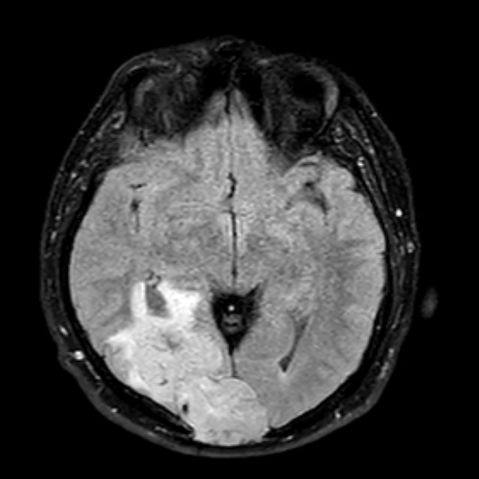

44 yaş, E

Baş ağrısı

Lenfoma

hemorajik glioblastoma multiforme (GBM, WHO Grade 4)